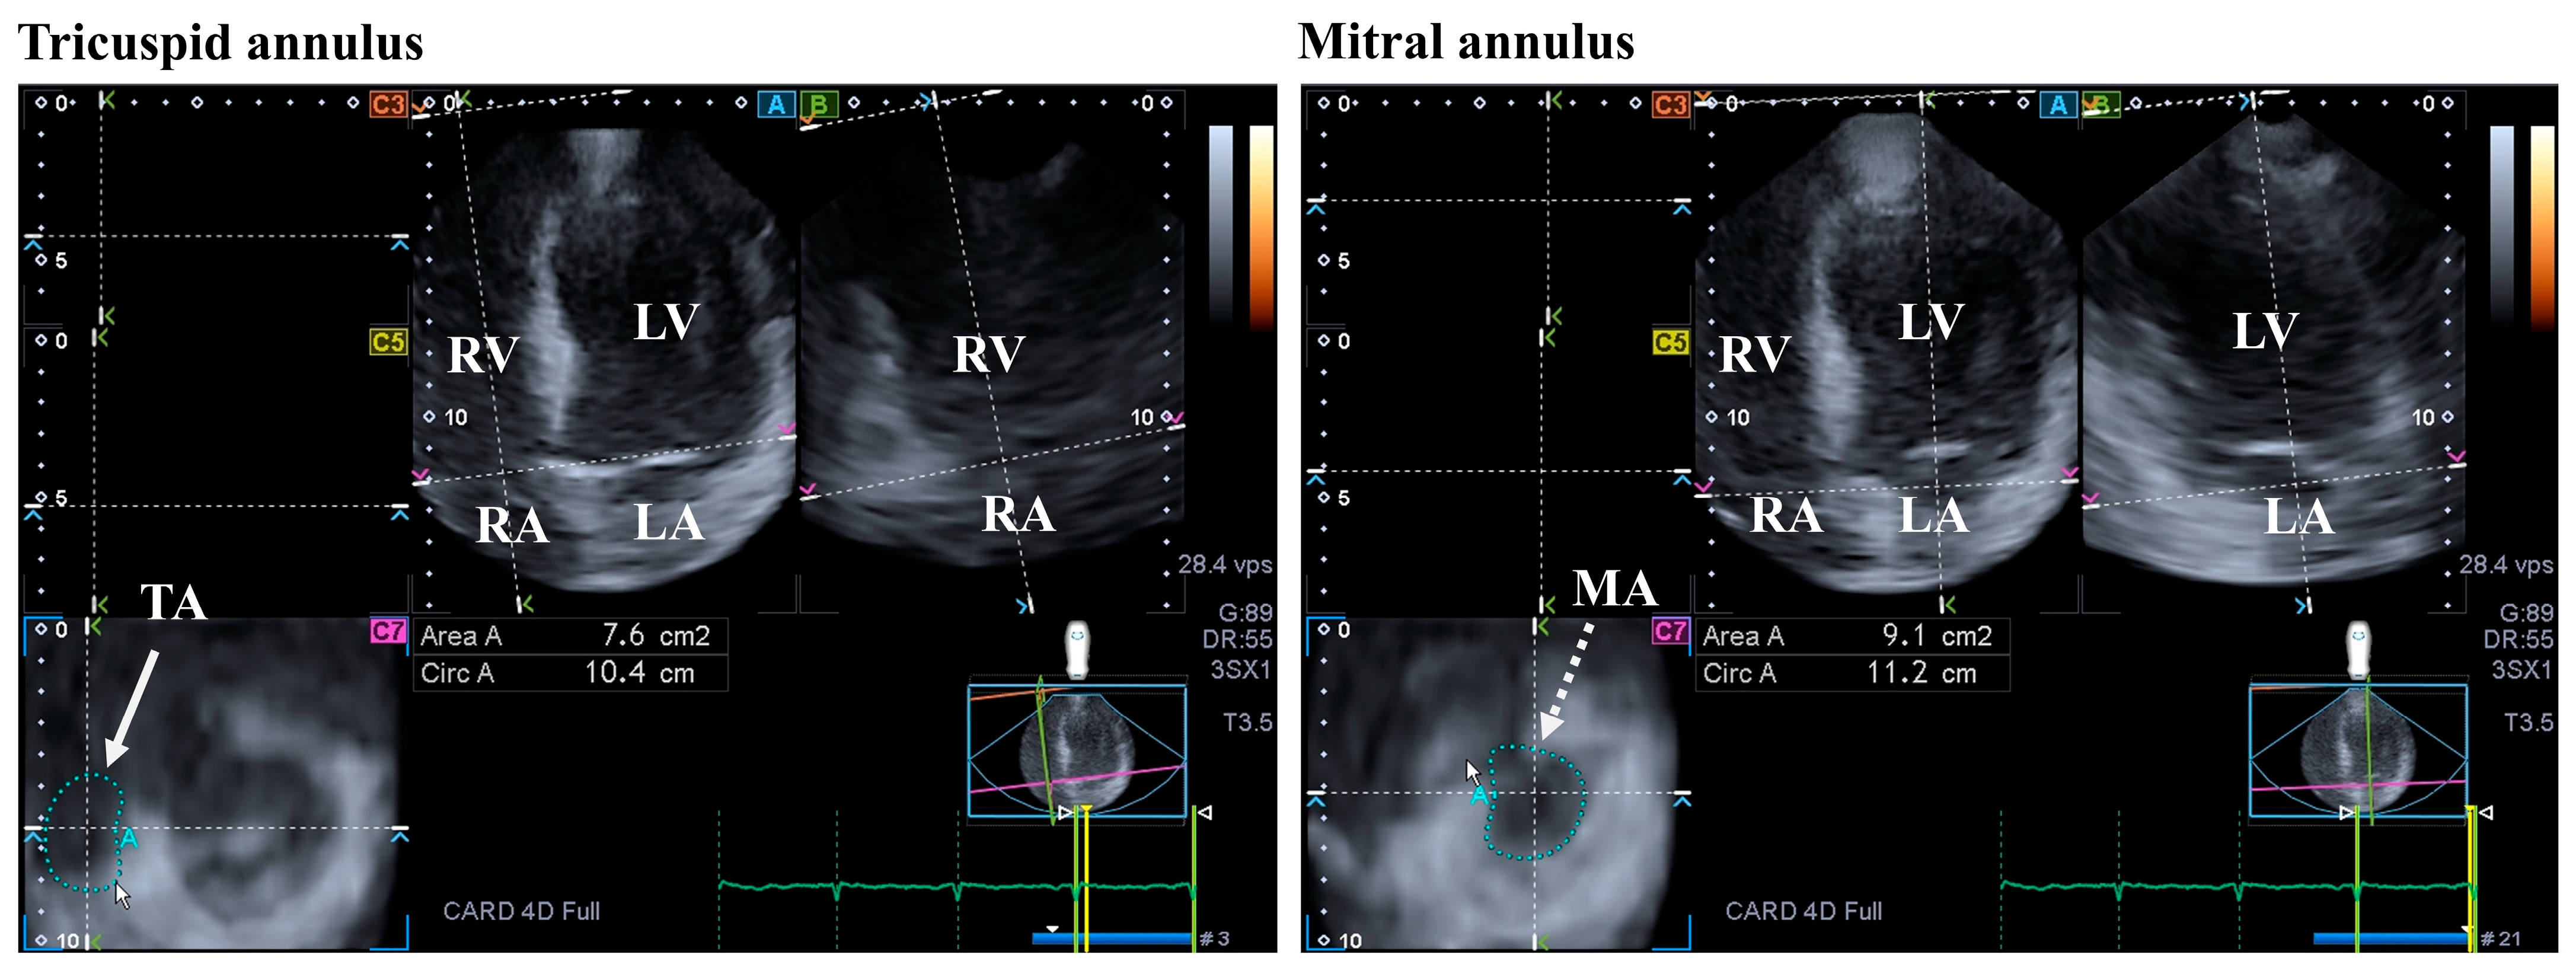

The MV is 3D saddle-shaped, with dynamic motion during the cardiac cycle. The MV is made up of the papillary muscles with tendinous chords, the posterior and anterior leaflets, and the fibrous mitral annulus (MA). It opens in the diastole, allowing a unidirectional flow from the LA to the LV, while it closes in the systole. The contraction of adjacent LA and LV myocardial areas considering the heart cycle and the timely occurrence of the contraction of the LA and LV is necessary for the proper contraction of the MA [34,35,36] (Figure 3).

Figure 3.

Evaluation of the tricuspid (TA) and the mitral annuli (MA) by three-dimensional (3D) speckle-tracking echocardiography. From the acquired 3D echocardiographic dataset, the following views are created: apical four-chamber (A) and two-chamber views (B) and a cross-sectional view at the level of the TA/MA optimized in apical four- and two-chamber views (C7). The white arrow represents the two-dimensionally projected TA plane, while dashed white arrow represents the two-dimensionally projected MA plane. Abbreviations: RV = right ventricle; RA = right atrium; LV = left ventricle; LA = left atrium; Circ = TA/MA perimeter; and Area = TA/MA area.

4.3. Tricuspid Valve

4.3.1. In Healthy Circumstances

The tricuspid valve (TV) is located between the RV and the RA, having a complex structure with a saddle shape. The TV performs dynamic movements throughout the heart cycle: it opens in the diastole and closes in the systole, without regurgitation. Important parts of the TV are the papillary muscles with tendinous chords, septal, anterior, and posterior leaflets, and the fibrous tricuspid annulus (TA), similar to the MV [46] (Figure 3).